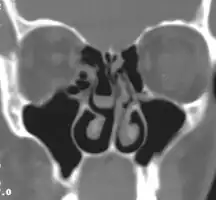

Bilateral concha bullosa, larger on the left